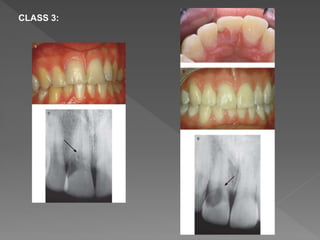

CLASS 3:

Radiologic signs:  Detectedon radiologic finding because tooth is usually asymptomatic.  Varies from asymmetrically located radiolucency with irregular margins in cervical/proximal region of tooth to uniformly round radiolucency centered over the root.  Early lesions are usually radiolucent in appearance.  Advanced lesions might have mottled appearance because of fibro-osseous nature of the lesion.  Root canal should be visible and intact (indicating lesion is external).

 Heithersay concludedthat classes 1–3 were treatable, but class 4 lesions were not amenable to treatment, and these cases would have benefited from alternative treatment such as extraction and replacement with an implant retained crown restoration.  In the instance of classes 1–3, the root canal should be nonsurgically accessed and temporarily occluded with a finger spreader or gutta-percha point.  Then the surgical repair to the resorptive defect might be carried out without blocking the root canal with filling material.  Heithersay recommended topical application of a 90% aqueous solution of trichloroacetic acid, curettage, and restoration with glass ionomer cement.